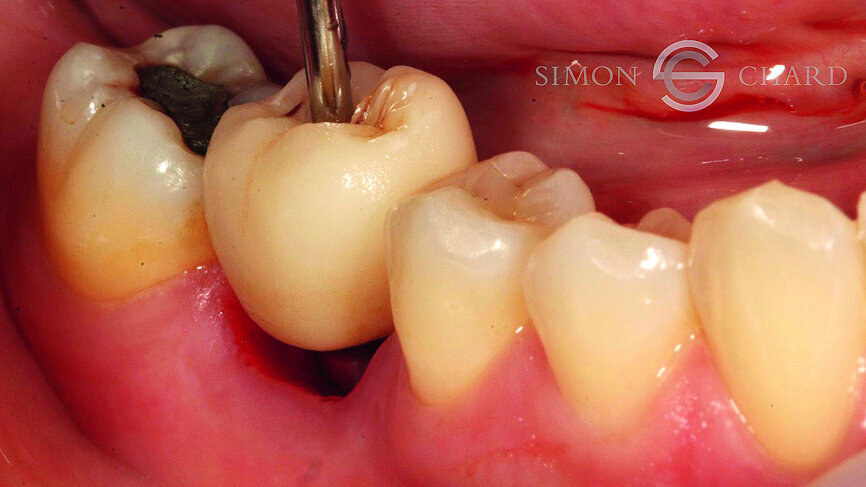

Traditionally, capturing the detail of this soft tissue profile with analogue methods is complicated and time consuming; however, utilising a digital intraoral scan (CEREC Omnicam) a “gingival mask scan” can be taken to accurately replicate this soft tissue and use it to guide the subgingival emergence profile of the restoration (Fig. 6).

Following removal of the temporary crown, a TiBase was placed into the fixture head and a scan body used as a reference point for the scanning of the implant (Figs. 7 & 8).